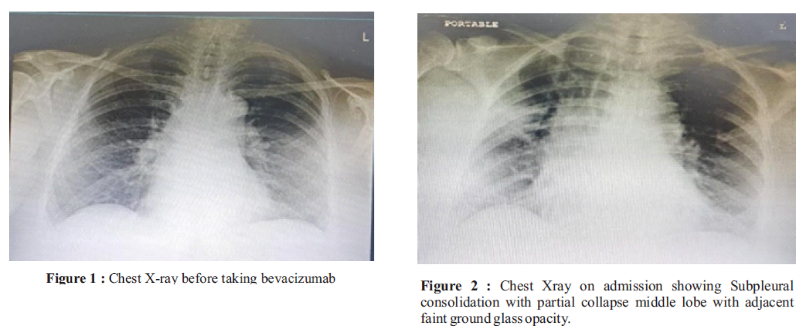

Bevacizumab-related pulmonary and renal adverse reactions: A case report

Savya Kurian, Bety C Byju, Lakshmi R, Madhu CS, Aditya V Boney (Author)